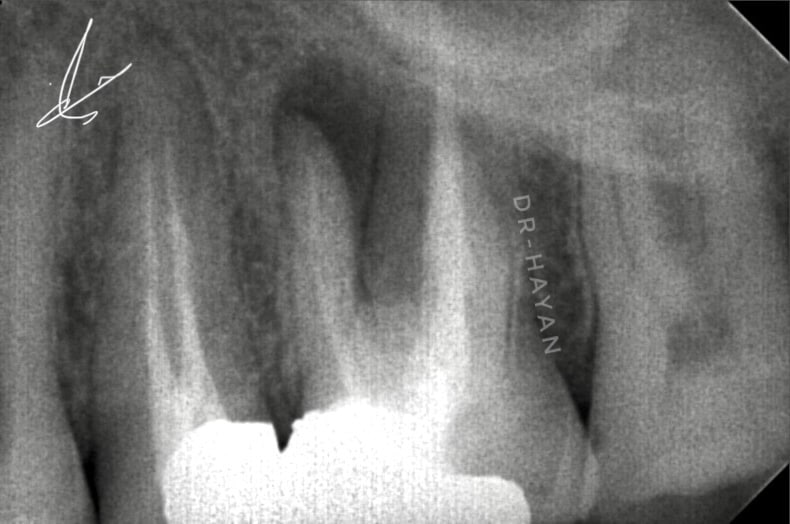

After 12 visit of irrigation protocol and intra canal medication

After completing drying the canal

Irrigation protocol for final obturation

WVC obturation by bio ceramic sealer